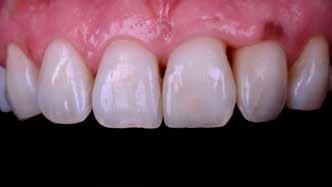

Egy teljes mosoly megtervezésekor vagy javításakor – akár közvetlenül, akár közvetve – a klinikus vagy a technikus alkotó, akinek feladata egy művészi remekmű létrehozása. Egy metszőfogtörés esetében azonban a klinikus kevésbé alkotó, mint inkább kovácsmester, akinek a környező és szomszédos fogazat minden optikai szempontját le kell utánoznia. Ez kihívást jelenthet az árnyalatválasztás szempontjából, mivel a legnagyobb színvariabilitás jellemzően a metszőfogak metsző harmadában található. Ez különösen igaz a fiatalabb páciensekre, akiknek gyakran van kiemelkedő áttetszőségük és opacitásuk ebben a régióban.

Több taktika is segíthet az összetett tömegek rétegződésének kezelésében ezekben a forgatókönyvekben. A palatális stent használata ennek egyik kiszámítható módja (1–4. ábra). Ennél a technikánál a törött területről egy modellen wax-up vagy mock-up készül, és egy gyurma PVS stentet vagy indexet állítanak elő. Ebből egy vékony réteg erős, félig áttetsző kompozit – tipikusan nano- vagy mikrohibrid – kerül a stentre, amely a szájpadlásfelületet reprodukálja. Ezt követően különböző opacitású és transzlucenciájú kompozitrétegeket rétegeznek az arcfelületre, így létrehozva egy zökkenőmentes restaurációt (1. a–c. ábra). Mivel viaszfelvételből készül, az okkluzális tényezőknek jól ellenőrizhetőnek kell lenniük. Ennek a technikának az a hátránya, hogy szükség van egy mock-upra, akár intraorálisan, akár egy modellen történő wax-up segítségével. Ez időigényes lehet, és második időpontot igényelhet, amely nehéz vagy nem praktikus, különösen gyermek- vagy sürgősségi páciensek esetében. Ezenkívül kis törések esetén a kompozittömegek behelyezése nehezebben megoldható, mint nagyobb törések esetén. Egy alternatív megközelítés az „üres vászon technika”, amely gyorsított polikromatikus helyreállítást biztosíthat kisebb törések, sürgősségi esetek vagy gyermekpáciensek esetében. Ez egy kromatikus mikrohibrid alapot használ, amelyet szükség esetén tinták vagy opakok követnek, és egy vékony réteg akromatikus mikrokitöltésű kompozit fed. A cél a törés elfedése és egy élethű, a környező fogazat transzlucenciájának és opacitásának megfelelő helyreállítás biztosítása.

Egy páciens elégedetlen volt a 8. fog incisofaciális felszínén lévő kéthetes restaurációval, mert úgy gondolta, hogy a központi metszőfogak nem illeszkednek egymáshoz. A vizsgálat során megállapították, hogy bár az egyszínű kompozit valóban megegyezett a fog alapszínével, további színre (árnyalatra) volt szükség a szomszédos fog utánzásához (4. ábra).

A fogakat nehéz latexmentes gumidámmal (Isodam, 4D Rubber) izolálták. A meglévő kompozitot eltávolítottuk; egy kromatikus mikrotöltésű kompozitot helyeztünk fel, és egy fehér színt (Creating Color, Cosmedent) vittünk fel egy #8-as K-résszel, vízszintes mozgással, hogy a vízszintes mintázatot lemásoljuk (5. ábra), ezután egy akromatikus mikrotöltésű kompozitot adtak hozzá. A 6. ábra az azonnali posztoperatív eredményt mutatja, a 7. ábra pedig a négyéves utóvizsgálatot, amely a mikrotöltött kompozit megmaradt fényét mutatja.